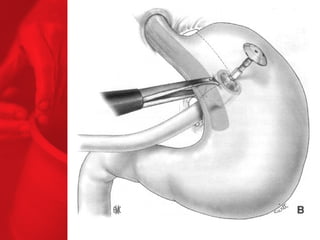

GASTRIC BYPASS Lesprocédures de malabsorption et restrictives > 56% de perte de poids excédentaire après quatre ans* > diminue le diabète de type 2 chez plus de 83 % des patients* *Christou NV, Sampalis JS, Liberman M, et al. Surgery Decreases Long-Term Mortality, Morbidity, and Health Care Use in Morbidly Obese Patients. Annals of Surgery 2004;240(3):416-424. ** Buchwald H, Avidor Y, Braunwald E, et al. Bariatric Surgery—A Systematic Review of the Literature and Meta-analysis. Journal of the American Medical Association 2004 Oct 13;292(14).

COMMENT FONCTIONNE LECOURT-CIRCUIT GASTRIQUE ? Facteurs chirurgicaux Restriction du volume des repas Certaine malabsorption Syndrome de chasse Réduction de l'appétit Facteurs pour les patients Apport en calories Dépense en calories BILAN ENERGETIQUE = apport alimentaire dépense en énergie

Echecs Malgré unebonne technique du CCGL, des échecs surviennent chez 15 à 20 % des patients. Les causes de reprise pondérale sont la dilatation de la poche gastrique, la dilatation de l'anastomose gastrojéjunale, l'hypertrophie des villosités du jéjunum proximal et la prise d'une alimentation avec des liquides à haute teneur en calories. Ainsi, pour les « superobèses » pathologiques (IMC > 50 kg/m2), l'intervention de référence pourrait devenir la diversion biliopancréatique.